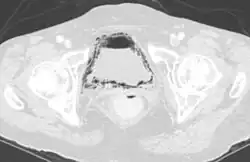

Ursächlich zugrunde liegt in einem Teil der Fälle eine Fistelbildung zwischen Harnblase und einem lufthaltigen Hohlorgan wie Dickdarm oder Scheide, die als Komplikation von chronisch-entzündlichen Darmerkrankungen wie dem Morbus Crohn,[1] eines operativen Eingriffes,[2] im Rahmen einer Divertikulitis[3] oder eines kolorektalen Karzinoms[4] auftreten kann. Bei Diabetikern kommen überdies selten Harnwegsinfektionen mit Mikroorganismen (Bakterien, Candida albicans) vor, welche die vermehrt mit dem Harn ausgeschiedene Glukose unter Gasbildung enzymatisch abbauen (emphysematöse Zystitis).[5][6]